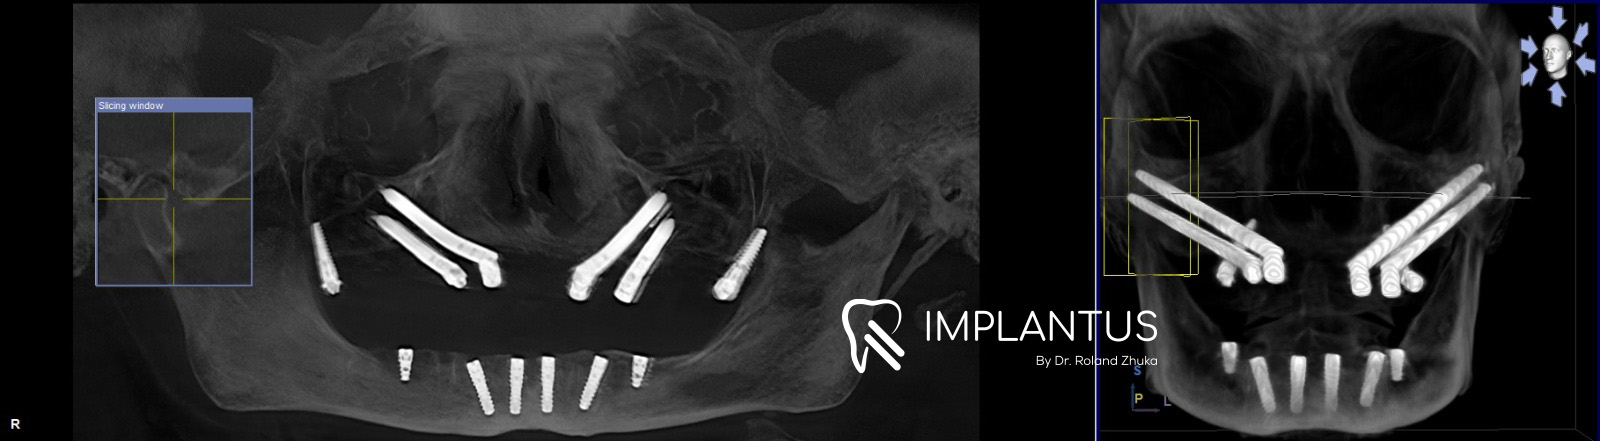

Pas vlerësimit klinik dhe radiologjik, u konstatua se kocka alveolare në nofullën e sipërme ishte e pamjaftueshme për vendosjen e implanteve konvencionale. Në këto raste, shumë paciente orientohen drejt procedurave të gjata dhe të pasigurta si:

Në këtë rast, zgjidhja më e sigurt dhe biologjikisht më e favorshme ishte shfrytëzimi i kockës skeletike, konkretisht:

• procesit zigomatik, • procesit pterigoid.

Këto struktura kockore janë shumë më të forta, stabile dhe rezistente, duke lejuar vendosjen e implanteve zigomatike dhe pterigoide, të cilat përfaqësojnë kulmin e implantologjisë së avancuar.

Ndërhyrja kirurgjikale për nofullën e sipërme zgjati rreth dy orë, kohë gjatë së cilës u vendosën implantet zigomatike dhe pterigoide në kockën skeletike, duke krijuar bazën e fortë për një rehabilitim fiks të menjëhershëm.